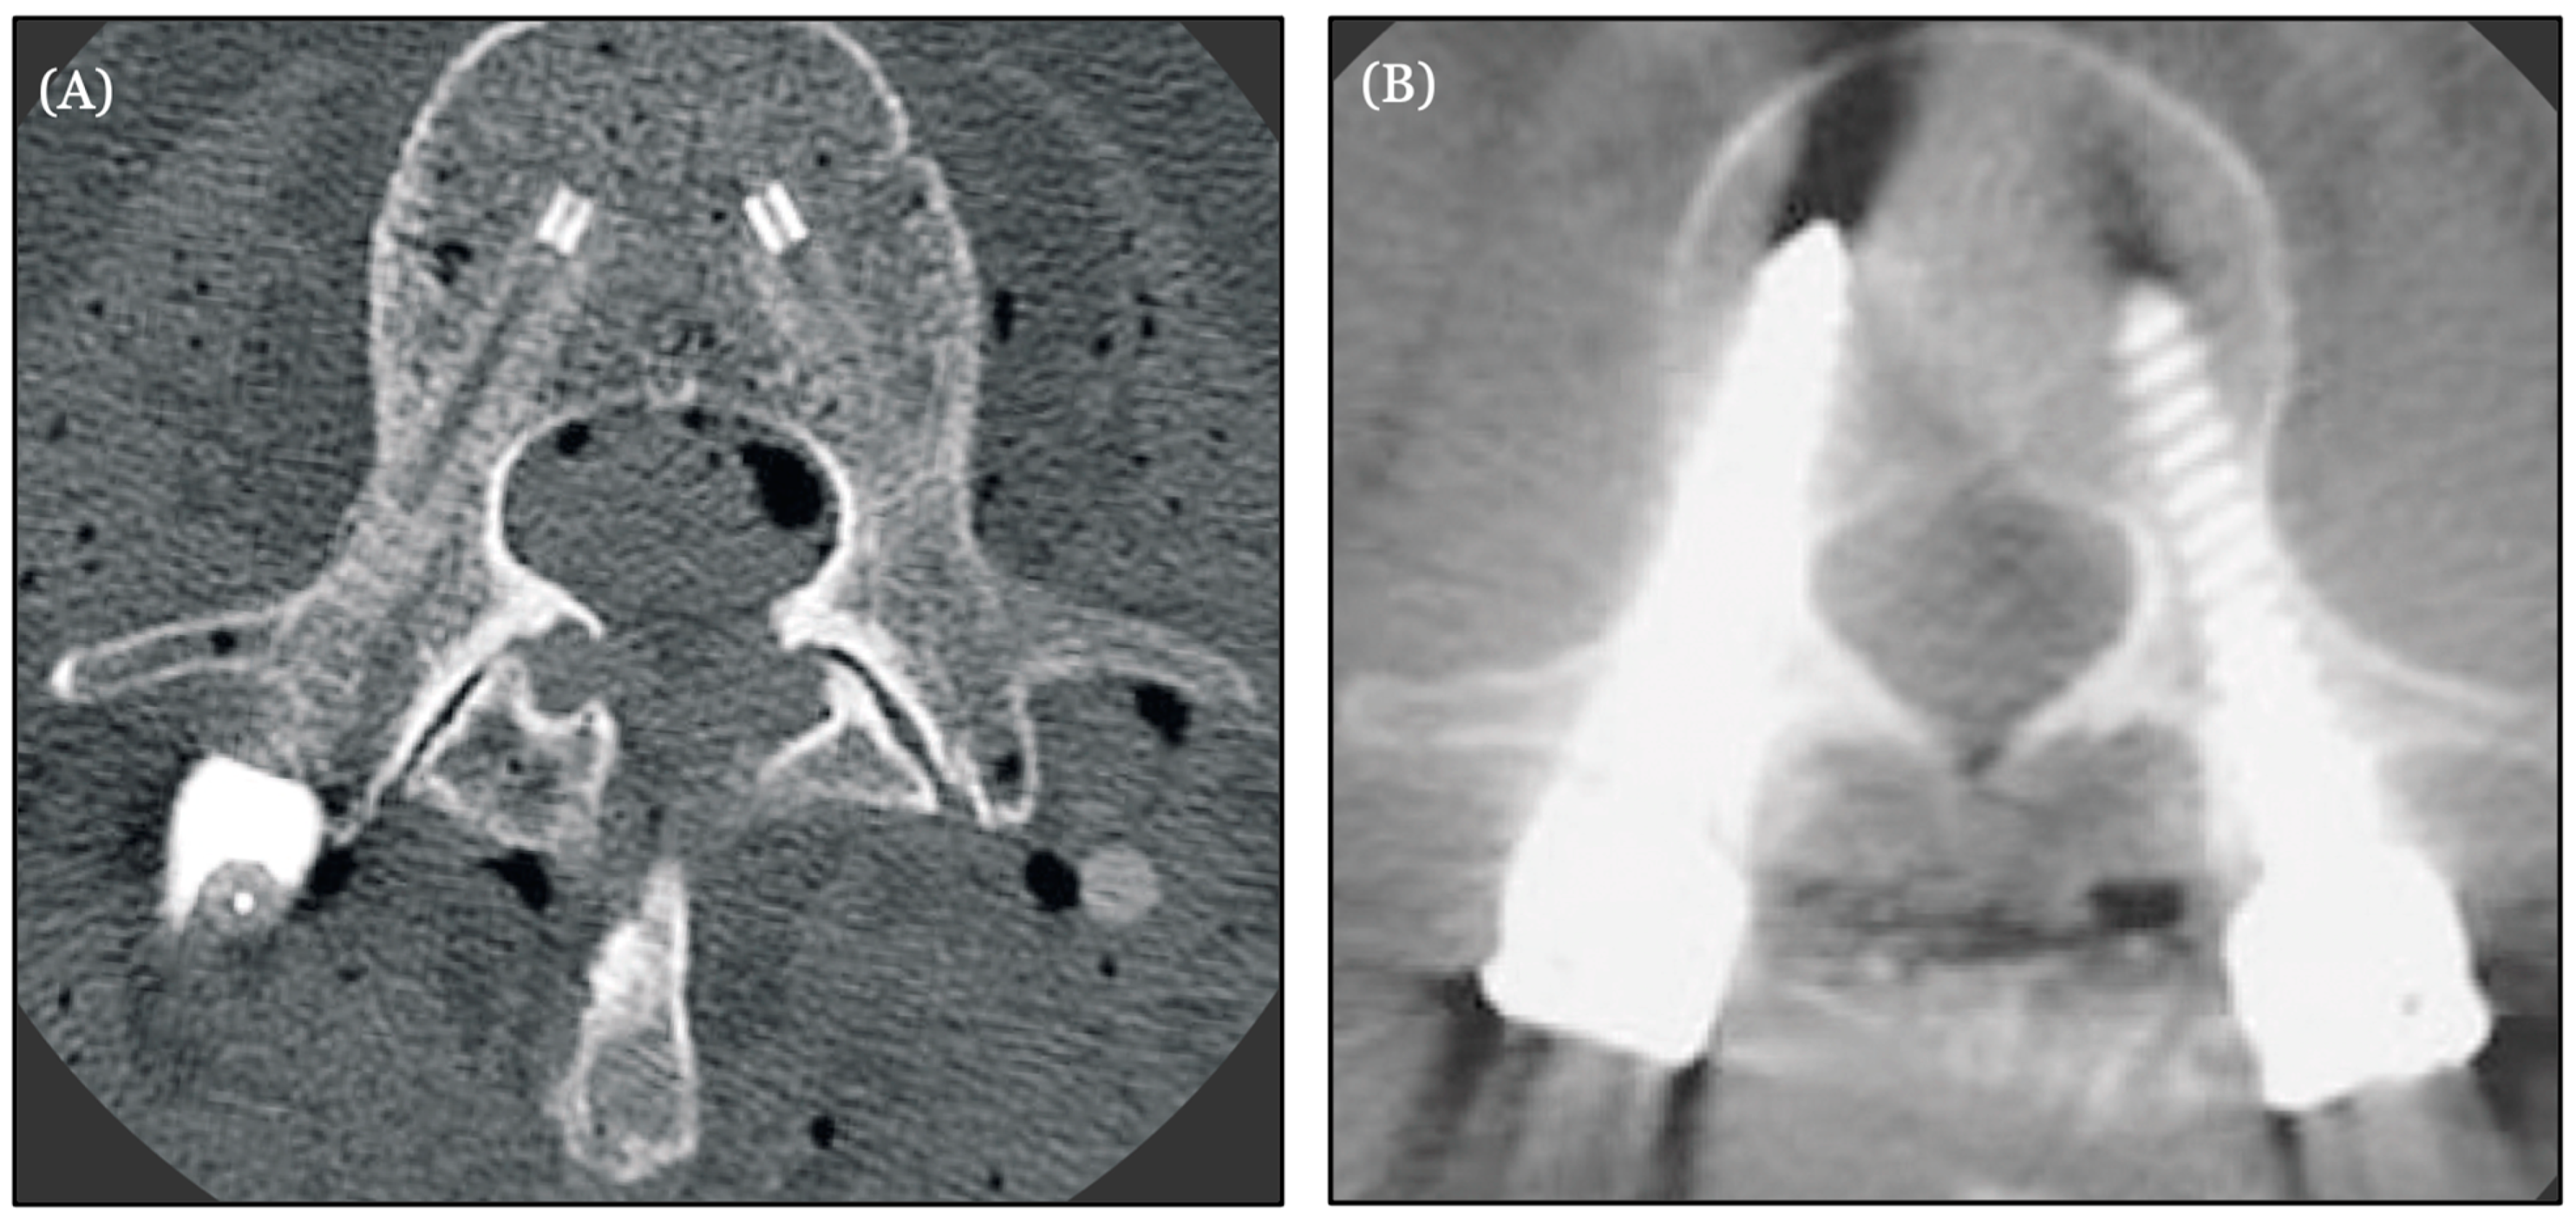

- Hubertus, V.; Wessels, L.; Früh, A.; Tkatschenko, D.; Nulis, I.; Bohner, G.; Prinz, V.; Onken, J.; Czabanka, M.; Vajkoczy, P.; et al. Navigation accuracy and assessability of carbon fiber-reinforced PEEK instrumentation with multimodal intraoperative imaging in spinal oncology. Sci. Rep. 2022, 12, 15816. [Google Scholar] [CrossRef] [PubMed] [PubMed Central]

| Hubertus et al. (2022) | Carbon fiber reinforced PEEK (CFR-PEEK) | Evaluation of the performance and precision of 3D intraoperative imaging and navigation systems in thoraco-lumbar instrumentation with CFR-PEEK pedicle screws | Navigation accuracy was considerably lower for CFR-PEEK pedicle screws than reported for titanium implants. CT may be the best imaging modality for CFR-PEEK instrumentation assessment [55] | N |